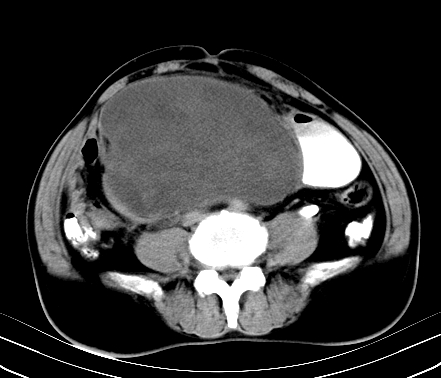

标题: CT19729B:男,74岁,因腿疼就诊,查体触腹部肿物,

增强扫描

动脉期

【ct表现】

1、肿块巨大,往往位于腹膜后,长大后才引起症状而就诊;那么位于腹膜后的肿瘤80%为恶性肿瘤。

2、实性肿瘤,增强扫描轻度不均强化,实性肿瘤一般不是好东西。

3、肿瘤边缘似见少许脂肪样密度。

4、腹膜后未见肿大淋巴结,但肿瘤于临近的肠管及组织接触紧密。

【诊断】

腹部占位,考虑位于腹膜后的恶性肿瘤,脂肪肉瘤(实体型)可能性大。

术后病理结果:腹膜后脂肪肉瘤。